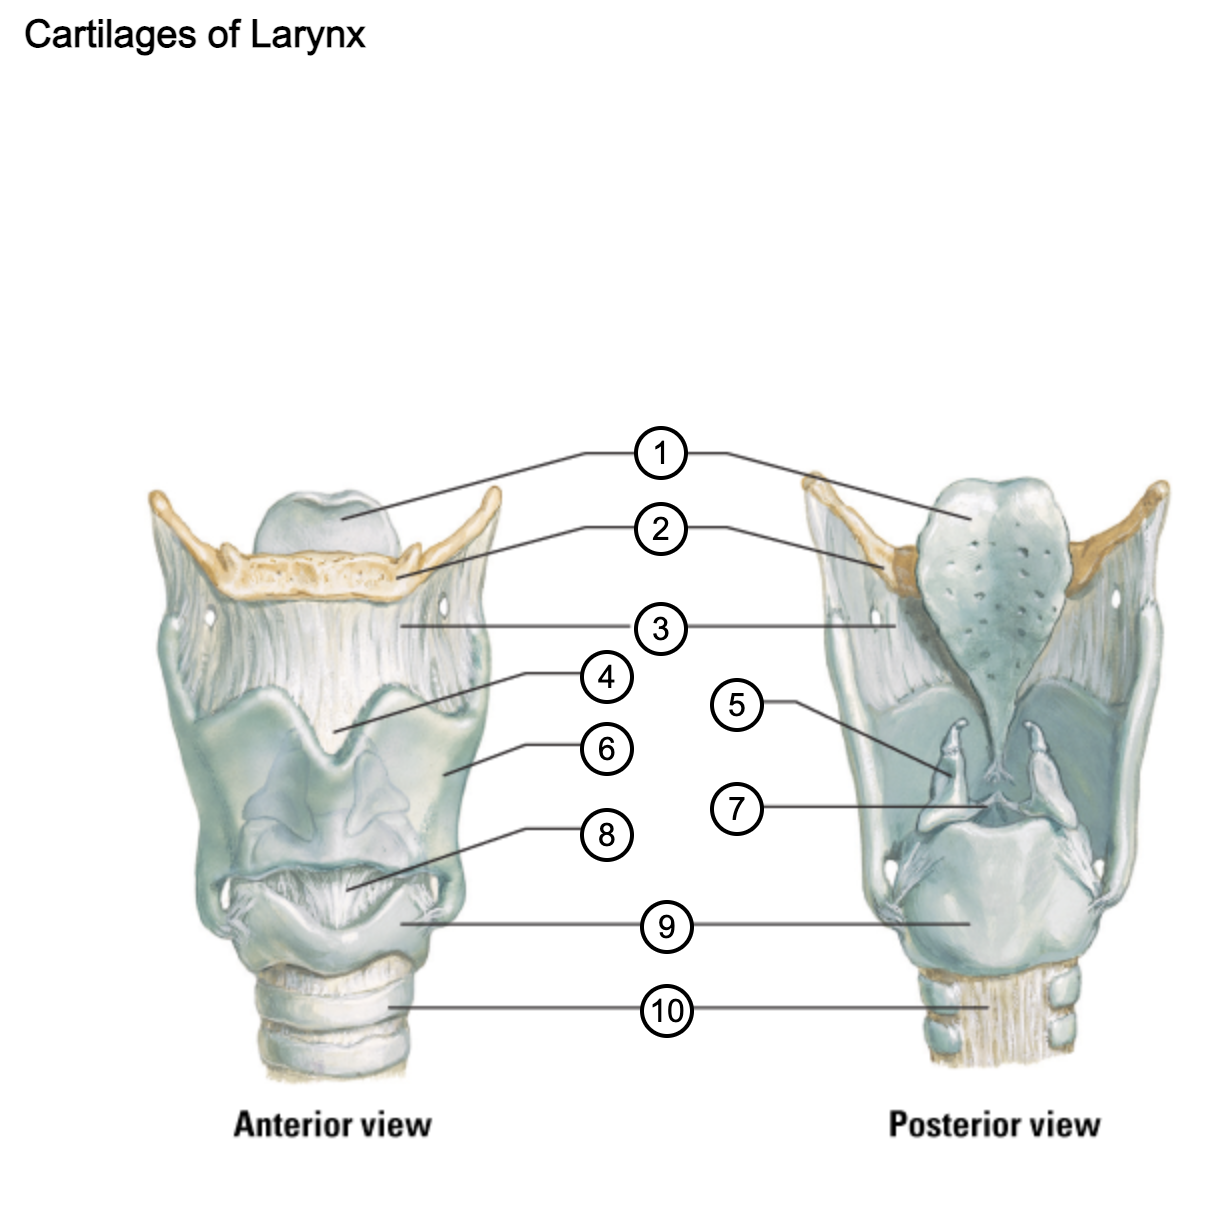

1

epiglottis

2

hyoid bone

3

thyrohyoid membrane

4

superior thyroid notch

5

arytenoid cartilage

6

lamina of thyroid cartilage

7

vocal ligament

8

median cricothyroid ligament

9

cricoid cartilage

10

trachea